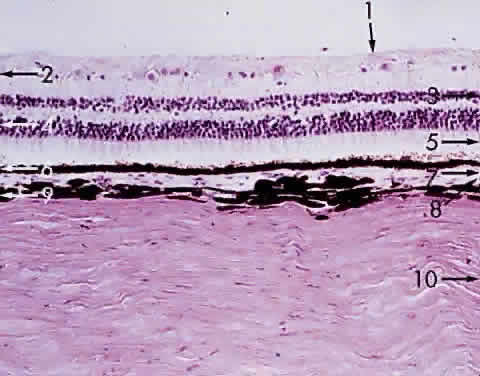

The choroid is a thin (0.2-mm), spongy, pigmented, vascular lamina. It is located between the sclera and the retina, extending from the ora serrata to the optic nerve (Fig. 15). Sensitive ultrasonographic techniques may detect increased thickness of the choroid as manifested by inflammation and neoplasms, focal or diffuse. Chromatophores are scattered within the choroid. The amount of pigmentation of the choroid determines the color of the fundus. Because the retina is transparent except for the blood vessels and the retinal pigmented epithelium (RPE), the variation in pigment accumulation within the choroid and retina determines the clinical picture of the ocular fundus. A heavily pigmented (negroid) fundus has the characteristic dark gray-green reflex, whereas a “blond” fundus has relatively little pigment and the pink choroidal vessel pattern is easily visible. Fluorescein and indocyanine green dye angiography readily provides clinicians with a means of evaluating the vascular integrity of the choroid and the changes that occur with disease. Also, the density of the choroidal pigmentation may affect the degree of retinal burn during photocoagulation of neovascular membranes.

Fig. 15. Choroid wedged between the retina and sclera: 1, internal limiting membrane of retina; 2, ganglion cell layer of retina; 3, bipolar cell layer of retina; 4, nuclei of rods and cones; 5, rod and cone layer of retina; 6, pigment epithelium of retina; 7, Bruch's membrane; 8, choriocapillaris; 9, large blood vessel of choroid; 10, sclera (× 225, KEI 8982B).